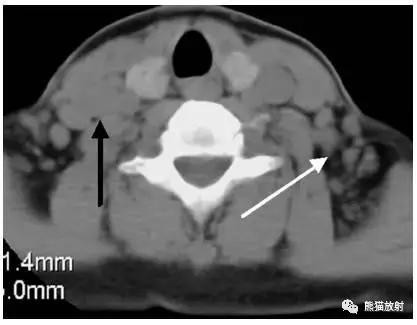

淋巴瘤。箭头显示右侧Ⅳ区,左侧Ⅴ区淋巴结增大。

淋巴瘤。黑箭显示双侧锁骨上窝淋巴结增大。